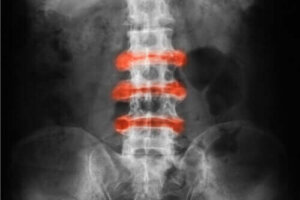

Ankilozan Spondilit, esas olarak sırt ve pelvis eklemlerinde meydana gelen inflamatuar artrittir. Akut rahatsızlıklar ve sertlik fiziksel aktivitelerle iyileşme eğilimindedir ve hareketsizlik durumu daha da kötüleştirebilir.

- Ankilozan spondiloartrit: Esas olarak omurgayı etkileyen inflamatuar artrit.